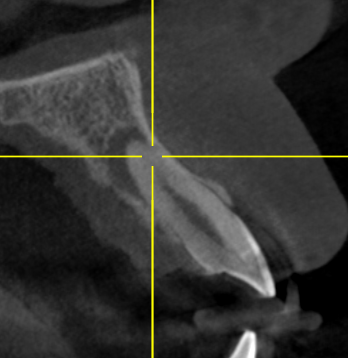

Клинический случай: пациент 21 год обратился с жалобами на боль и отек в области переднего зуба. На снимке КТ выявлено обширное воспаление (более 5мм диаметре) Проведено эндодонтическое лечение по протоколу с введением лечебной пасты на 14 дней.

киста на верхушке корня 12 зуба (очаг деструкции костной ткани)

На контрольном снимке спустя 4 месяца киста полностью зажила. Зуб спасен, пациент счастлив. Работу выполнил врач Белым Елена Сергеевна.